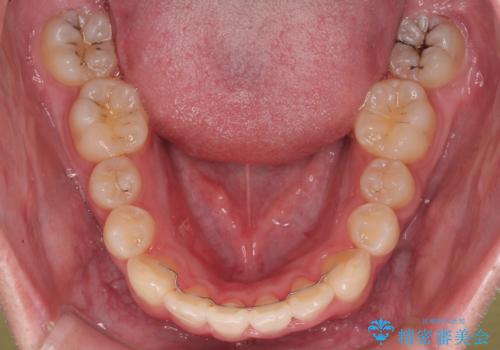

初診時の状態

・上下ともに歯がきれいに並びきらず、がたつきが見られました。

・上下の前歯の中心(正中)がずれています。

・特に上顎の幅が狭いため、下顎の歯列も内側に入り込み、歯が並ぶスペースが不足していました。